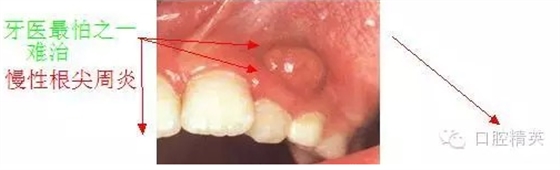

首頁牙體牙髓 慢性根尖周炎的臨床合理治療

慢性根尖周炎的臨床合理治療

慢性根尖周炎指牙齒根尖部及其周圍組織的慢性感染性病變的總稱。大多數(shù)由牙髓壞疽而來,一部分因急性根周炎未經(jīng)徹底治療而轉(zhuǎn)成。根管內(nèi)由于長期有感染及病原刺激存在,根尖周圍組織呈現(xiàn)慢性炎癥反應,表現(xiàn)為炎性肉芽組織形成和牙槽骨破壞。一旦清除根管內(nèi)的病原刺激物,根尖周組織所受到的損害又是可以修復的。

慢性根尖周炎治療療程較長,部分人由于沒有充足的時間而放棄治療,導致一些可行使功能的牙齒被拔除,影響了咀嚼。對如何保存牙齒的功能并相對減少復診次數(shù),筆者在十余年的工作中總結(jié)了一些經(jīng)驗,先將慢性根尖周炎的臨床合理治療經(jīng)驗介紹如下。